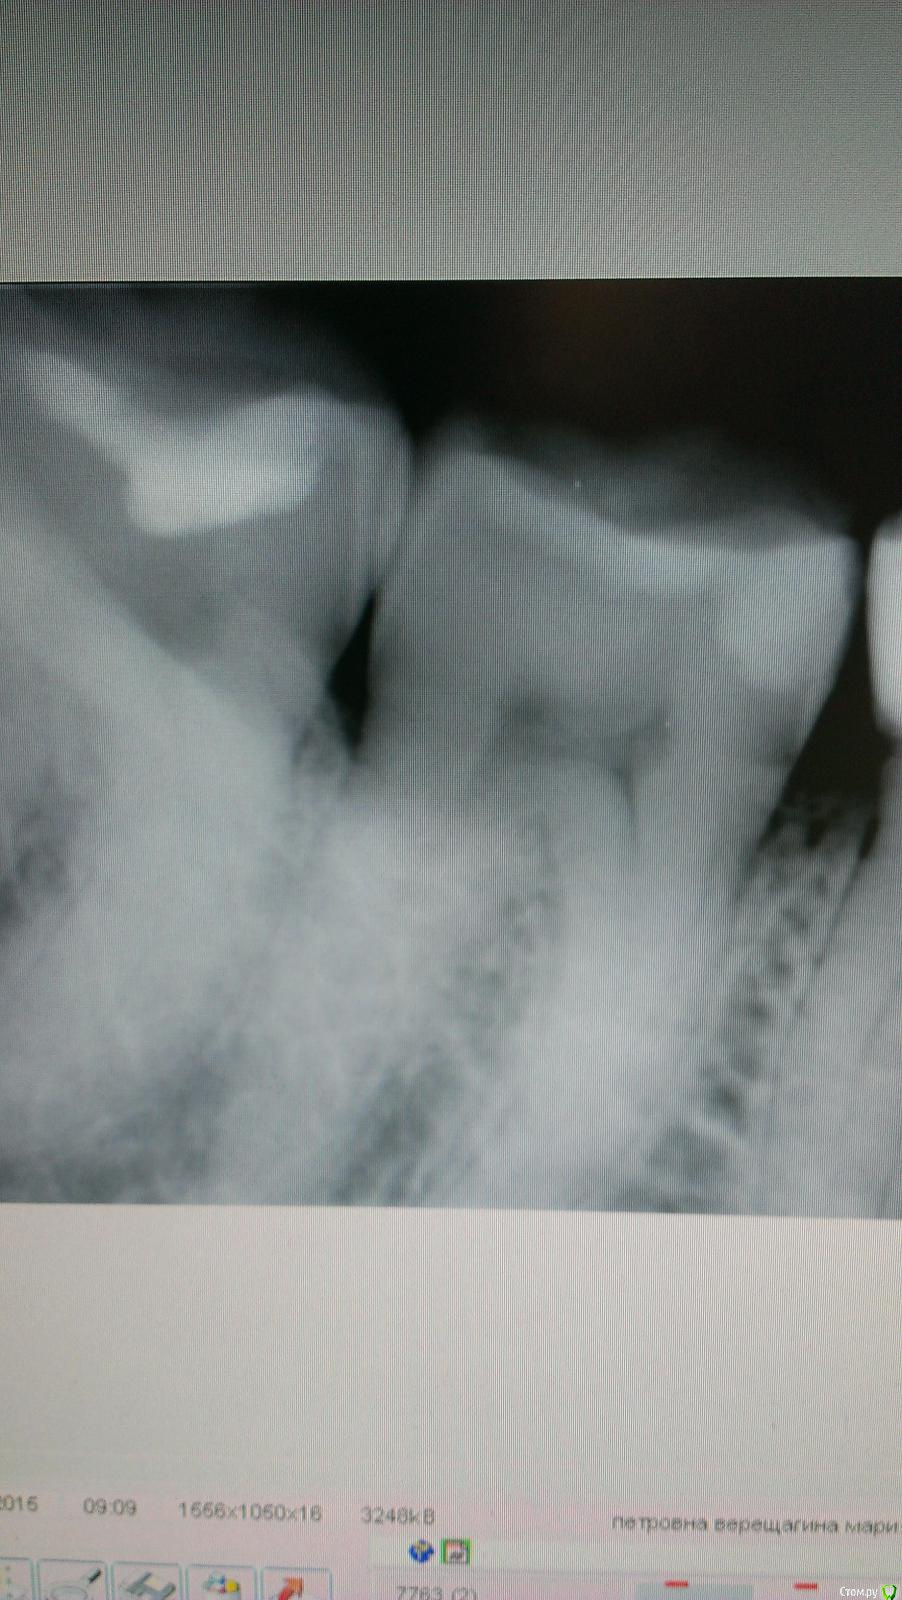

Girl Опубликовано 10 июня, 2015 Поделиться Опубликовано 10 июня, 2015 (изменено) Обратилась пациентка с болью на холодное между 47 и 48.47 лечен год назад по кариесу, на жеват пов-ти пломба. 48 тоже лечен не знаю когда, тоже на жевательной пломба и вторичный кариес. Между зубами реакция на холод и зондирование. Вот снимок. Это 47? У него вроде полость на дистальной пов-ти. Изменено 10 июня, 2015 пользователем Girl Ссылка на комментарий

red_butler Опубликовано 10 июня, 2015 Поделиться Опубликовано 10 июня, 2015 Меняйте все, на шестом вижу дефект или рецидив кариесаДа, фамилия пациентки в открытом доступе, не к чему Ссылка на комментарий